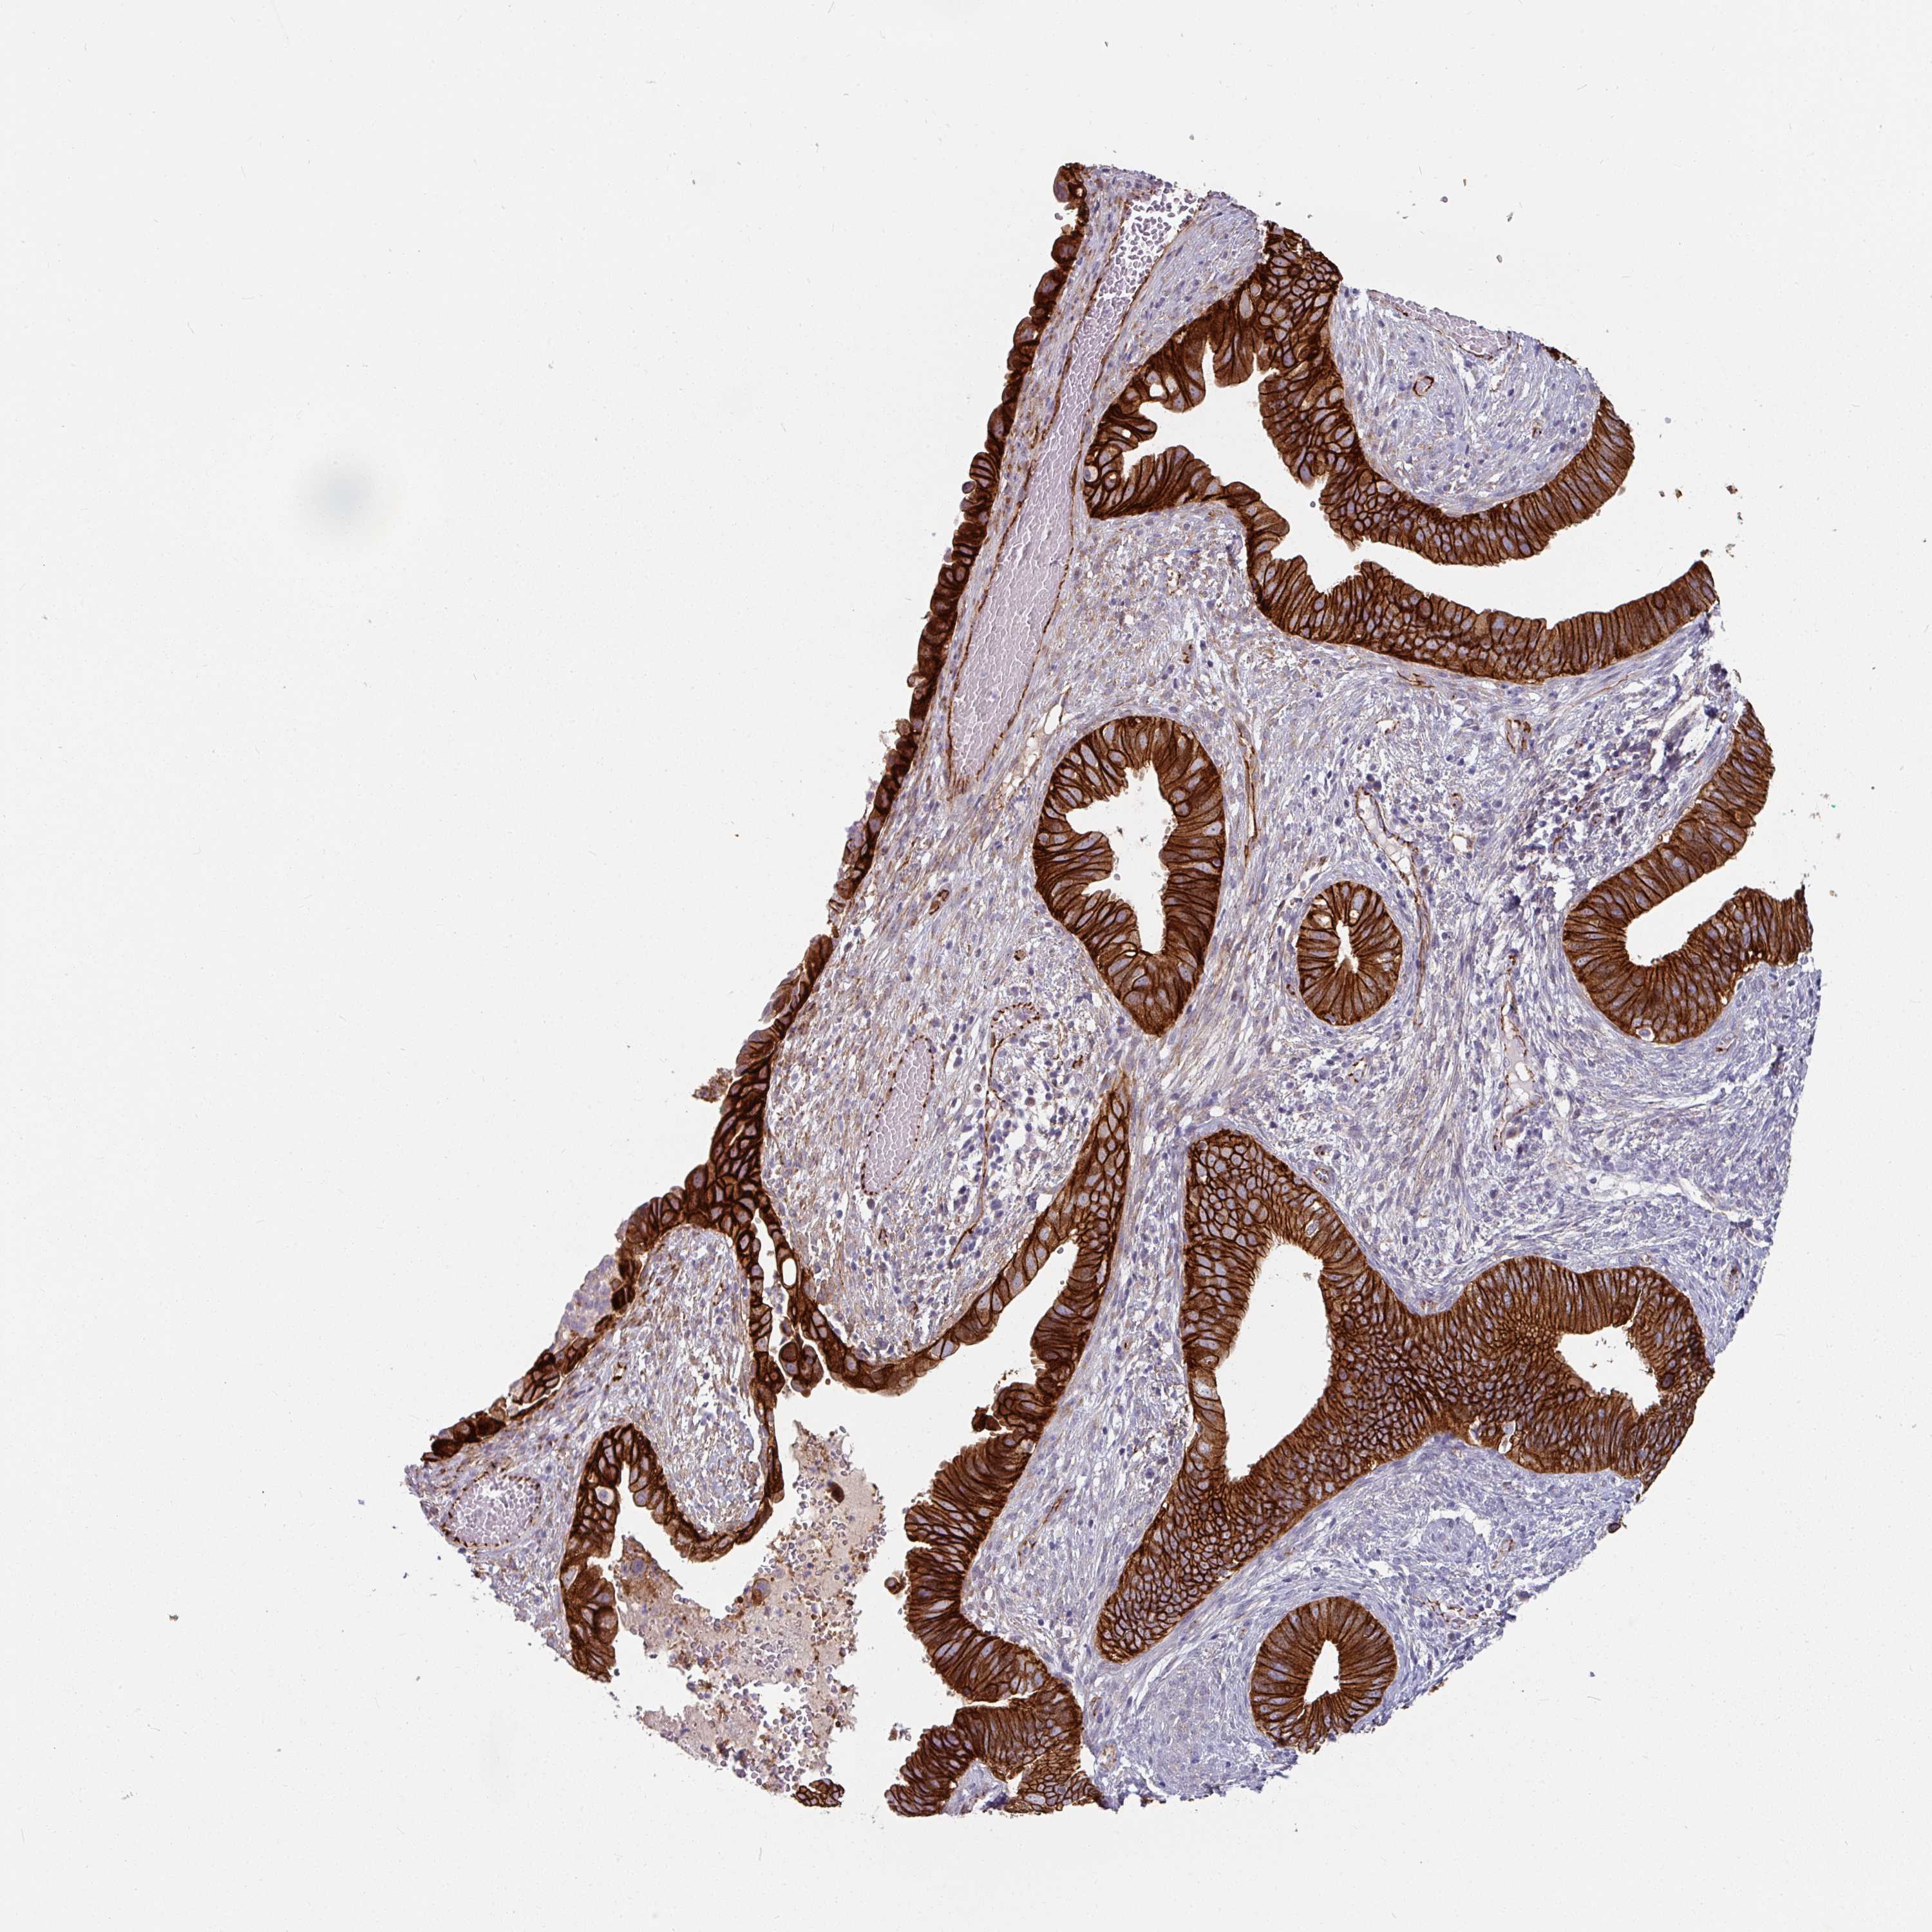

CERVICAL CANCER - Protein expressioni

A mouse-over function shows sample information and annotation data. Click on an image to view it in a full screen mode. Samples can be filtered based on level of antibody staining by selecting one or several of the following categories: high, medium, low and not detected. The assay and annotation is described here.

Note that samples used for immunohistochemistry by the Human Protein Atlas do not correspond to samples in the TCGA dataset.

Antibody stainingi

Antibody staining in the annotated cell types in the current human tissue is reported as not detected, low, medium, or high, based on conventional immunohistochemistry profiling in selected tissues. This score is based on the combination of the staining intensity and fraction of stained cells.

Each image is clickable and will lead to virtual microscopy that enables deeper exploration of all samples and also displays staining intensity scores, fraction scores and subcellular localization as well as patient and tissue information for each sample.

Antibody HPA032047

Antibody CAB002139

Squamous cell carcinoma, NOS

Adenocarcinoma, NOS